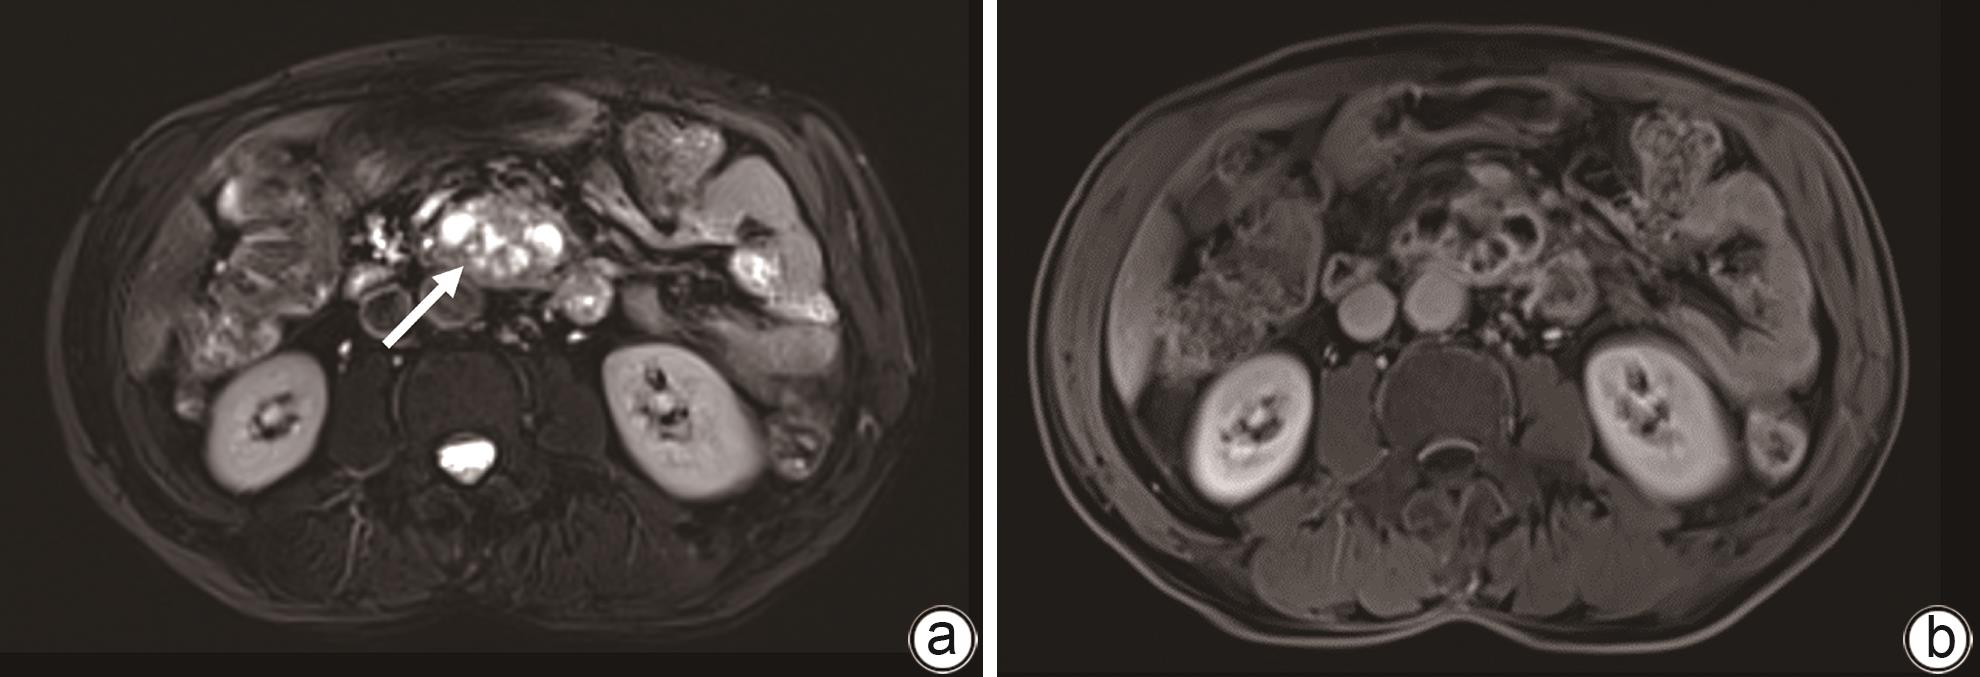

Clinical effect of Foley catheter through sinus tract in treatment of complex pancreatic fistula with massive venous hemorrhage after pancreaticoduodenectomy: A case report

2024, 40(11): 2283-2287. DOI: 10.12449/JCH241123

Abstract:

At present, vascular intervention and surgery are the main methods for the treatment of pancreatic fistula with bleeding after pancreaticoduodenectomy, but these treatment methods have certain drawbacks, such as the complications of pancreatic fistula, bleeding, and abdominal infection after surgical treatment, and interventional treatment sometimes fails to identify the bleeding site. This article reports a case of complex pancreatic fistula with massive venous hemorrhage after pancreaticoduodenectomy treated with Foley catheter balloon compression through the drainage tube sinus. Bleeding was arrested and gastrointestinal fistula was cured after catheter balloon compression and effective drainage, with no complications such as pancreatic pseudocyst, intestinal ischemia, and portal hypertension.